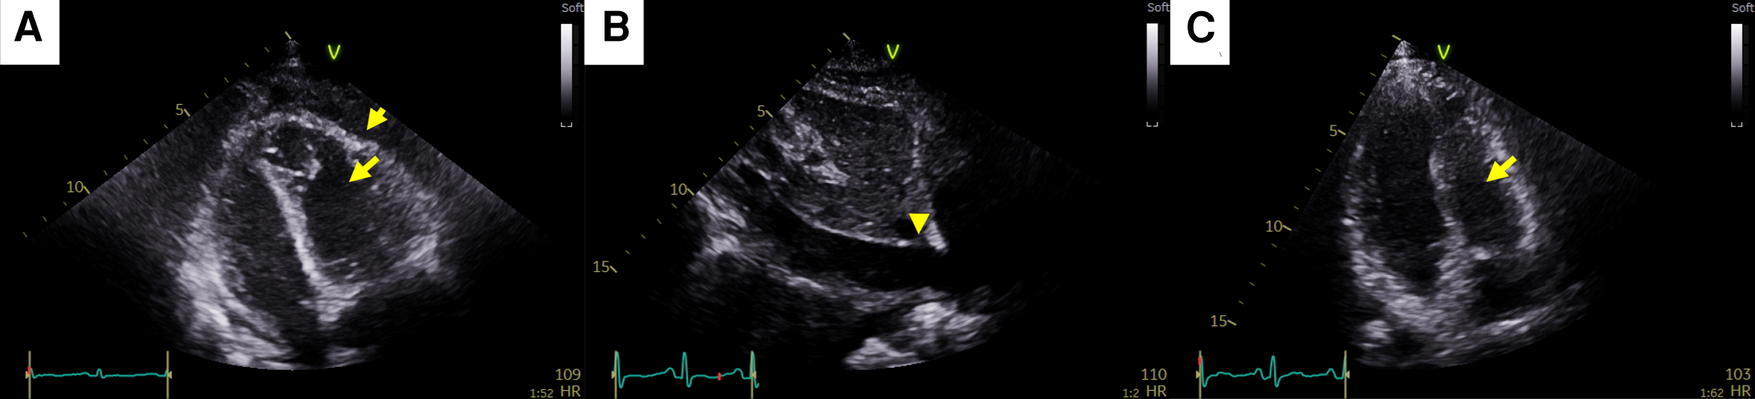

A 35-year-old female patient who had been undergoing palliative chemotherapy with gemcitabine and cisplatin for HER2-positive MBC was referred to the Department of Cardiology for New York Heart Association (NYHA) class IV dyspnea. Her blood pressure was within the normal range (110/80 mmHg); however her pulse rate was elevated, reaching 124 BPM. The NT-proBNP level was slightly elevated (249 pg/ml). Echocardiography revealed a large PE with definite tamponade physiology, though only a small PE was detected on the chest computed tomography (CT) one month ago (Figures 3A,B, Supplementary Video 5). Emergent pericardiocentesis was performed on the same day, and a metastatic adenocarcinoma was identified in the PE cytopathology, without other possible causes of PE, similar to Case 1. Two days after the pericardiocentesis, her dyspnea only modestly improved (NYHA class III) and her NT-proBNP level was markedly elevated (4,230 pg/ml). Follow-up echocardiogram showed pericardial adhesions and thickening around the entire cardiac border with CP. Additionally, the right ventricular free wall was captured to the adjacent pericardium, which resulted in right ventricular systolic dysfunction (Figure 4A, Supplementary Video 6). Both CP and right ventricular systolic dysfunction resulted in plethora of the inferior vena cava (Figure 4B). AIT against ECP was also introduced for this patient using prednisolone and colchicine (the same regimen as in Case 1). Despite pericardial metastasis, chemotherapeutic regimen was maintained without changes, simultaneously with AIT because the overall cancer was relatively stable, except for pericardial metastasis. At the 14th day of AIT, her dyspnea completely resolved (NYHA class I), and the NT-proBNP level rapidly decreased to 1,650 pg/ml. After 2 months of AIT, the NT-proBNP level decreased (245 pg/ml), and follow up echocardiogram showed complete resolution of pericardial thickening, adhesion, CP, and right ventricular dysfunction (Figure 4C, Supplementary Video 7). This patient is still receiving chemotherapy with gemcitabine and cisplatin for 9 months, without recurrence of CP, need for repeated pericardiocentesis, or cancer progression.

Figure 4

Pericardial changes after pericardiocentesis in case 2. (A) Pericardial adhesions and thickening (short arrow) causing constrictive physiology (CP). The right ventricular free wall was captured to the adjacent pericardium, which resulted in right ventricular systolic dysfunction (long arrow). (B) Plethora of the inferior vena cava caused by both CP and right ventricular systolic dysfunction (arrowhead). (C) At the end of anti-inflammatory treatment, pericardial adhesions, thickening, CP, and right ventricular dysfunction (arrow) were completely resolved.